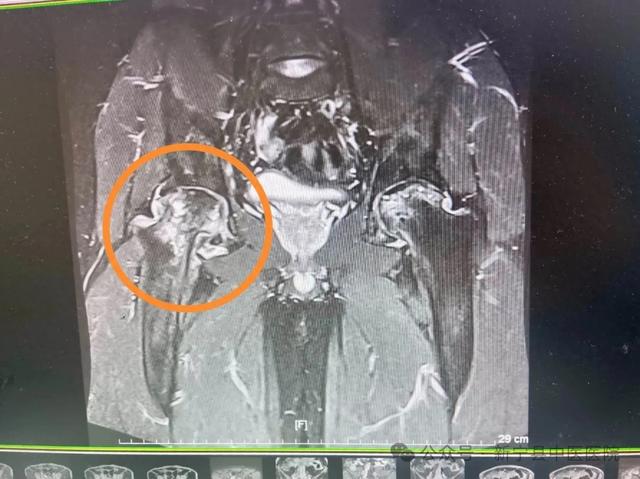

经人介绍新宁县中医医院是湖南省重点骨伤专科 , 治疗骨伤疾病有先进的医疗技术 , 为此 , 张先生专程来到新宁县中医医院骨伤二科 , 找到郭刚文教授、徐波主任 。 经骨盆DR检查 , 他双侧股骨头坏死 , 右侧为重 , 股骨头已严重塌陷 , 髋关节半脱位 , 髋臼磨损 。

徐波主任介绍 , 股骨头缺血性坏死亦称股骨头无菌性坏死 , 因创伤、酗酒、激素等多种原因导致股骨头血供中断或受损 , 引起骨细胞及骨髓成分死亡及随后的修复 , 继而导致股骨头结构改变、股骨头塌陷、关节功能障碍的疾病 , 因其治疗周期长、致残率高 , 又有“不死的癌症”之称 。

(▲术后拍片复查)